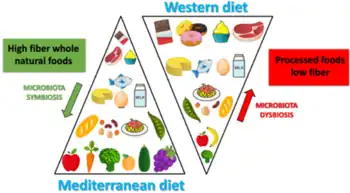

Individuals play an important role in maintaining their cognitive health. One way to achieve this is by the promotion of healthy nutrition. In particular, the Mediterranean diet, defined as being low in saturated fat and high in vegetable oils, showed improvement in aspects of cognitive function. This diet consists of low intake of sweets and eggs, moderate intakes of meat and fish, dairy products and red wine, and high intake of leafy green vegetables, pulses/legumes and nuts, fruits, cereal, and cold pressed extra virgin olive oil.[7] Further analysis concluded that the Mediterranean diet supplemented by olive oil resulted in better cognition and memory as compared to the Mediterranean diet plus mixed nuts combination.[26]